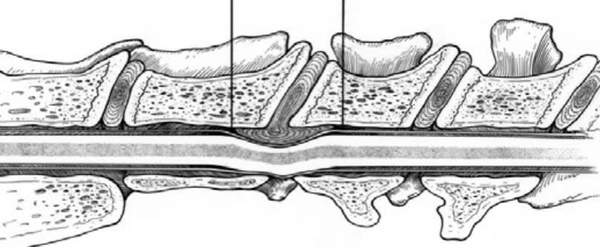

Ý nghĩa lâm sàng của xoang tĩnh mạch xương sống trong phẫu thuật cột sống cổ:

- Hình ảnh chế phẩm latex giúp làm rõ vị trí của xoang tĩnh mạch xương sống ở đáy ống cột sống. Khi loại bỏ mảng xương sống phía trên, ta có thể thấy đĩa đệm (màu cam) và sự tụ tập của các xoang tĩnh mạch ở giữa thân đốt sống, tách ra phía trên đĩa đệm.

- Điều này nhắc nhở chúng ta rằng khi thực hiện phẫu thuật từ phía bụng, cần đặc biệt hạn chế chiều rộng khoang phẫu thuật để tránh tổn thương các xoang tĩnh mạch. Nếu tổn thương, nguy cơ chảy máu nhiều là rất cao.

- Khuyến nghị phẫu thuật:

- Chiều rộng khoang mổ không vượt quá 50% chiều rộng thân đốt sống để bảo toàn tính ổn định.

- Chiều dài khe mở không nên vượt quá điểm giữa của thân đốt sống, vì ở giữa là vị trí gần nhất của hai xoang tĩnh mạch cạnh thân đốt sống.